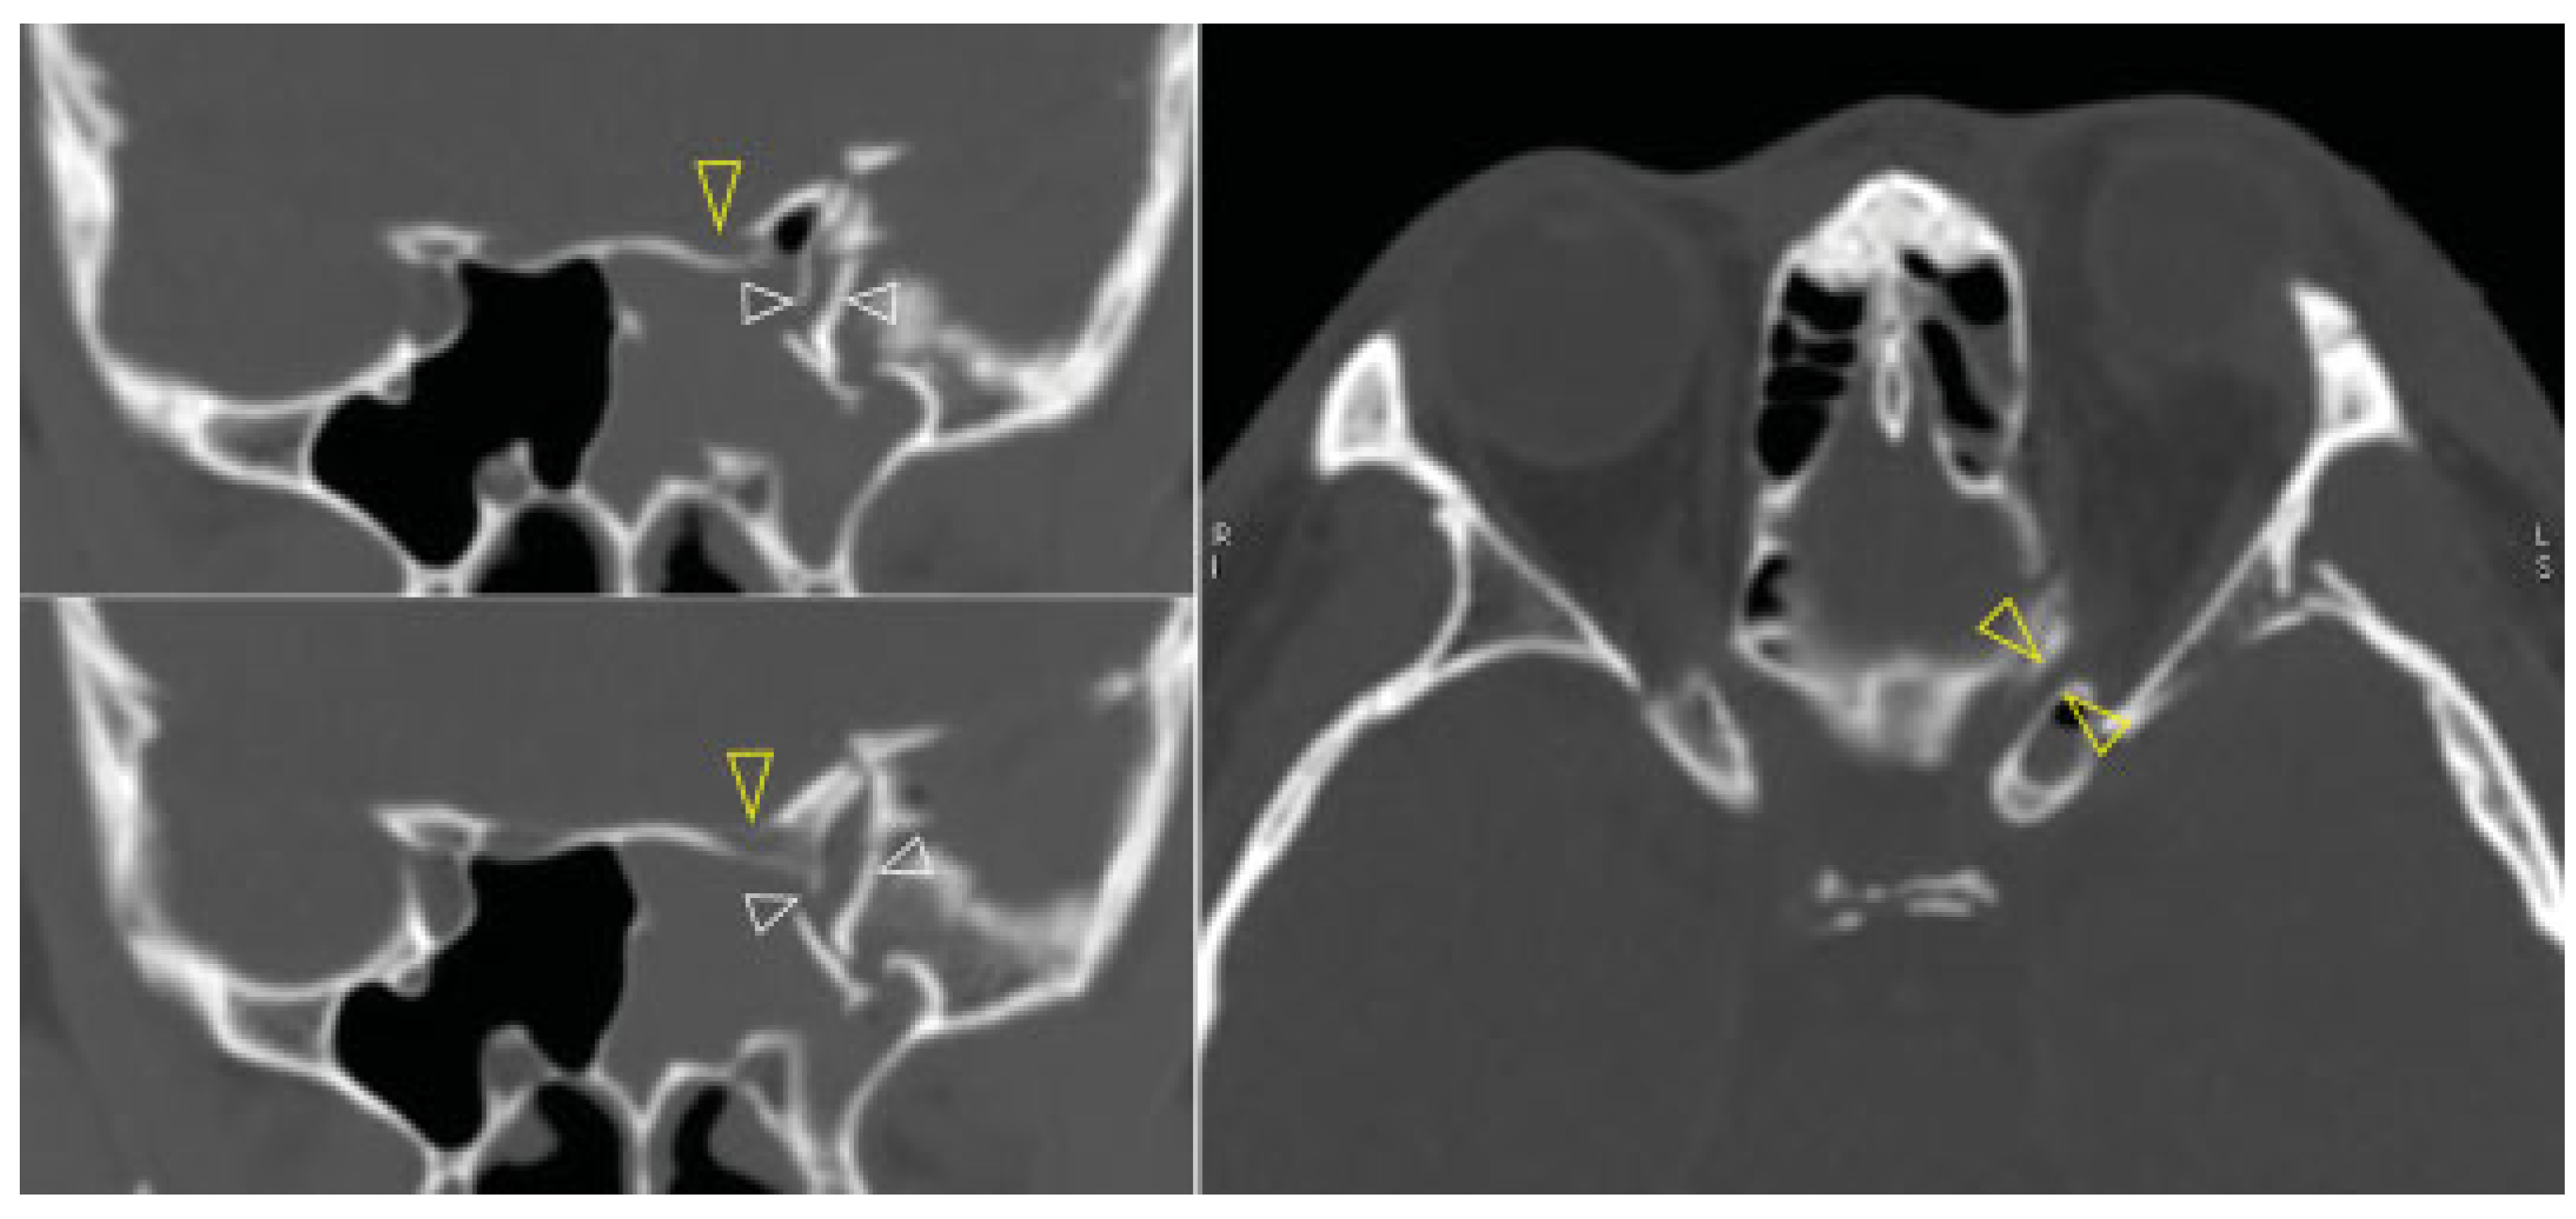

Computed tomography (CT) revealed a left sided orbital and ZMC fracture of the blow-in type, in which the inward displacement of the fractured segments results in decreased orbital volume; there was resultant proptosis of the left eye globe (Figure 2). The superior orbital fissure was compressed by the medially displacement of the fractured segment of the greater wing of the left sphenoid (Figure 3, left). This medially displaced fragment pushed the left anterior clinoid process further medially and caused it also to fracture, which subsequently resulted in optic canal fracture and optic nerve compression (Figure 3, right). A slight left temporal epidural hematoma was also noted. The diagnosis was made of the left blow-in type of orbital and ZMC fracture with associated orbital apex syndrome, due to direct compression of the optic canal and the superior orbital fissure from the displaced fracture fragments.

Figure 3.

Preoperative CT (Left, upper and lower) superior orbital fissure compression by the medially displaced fracture segment of the greater wing of the left sphenoid (white arrowheads), (right) optic canal fracture and nerve compression (yellow arrowheads).